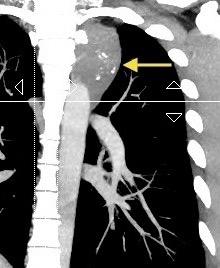

Participación de la V. Ácigos como vía principal para llegar a la VCI.

Visible: 88%

Depresión ligera…….55% profunda. 35%

FRECUENTES Ganglios. (más frecuente)

Webb R. 2005 Aneurisma aórtico Disección aórtica con aneurisma Masa mediastínica (incl. Ca. de pulmón)